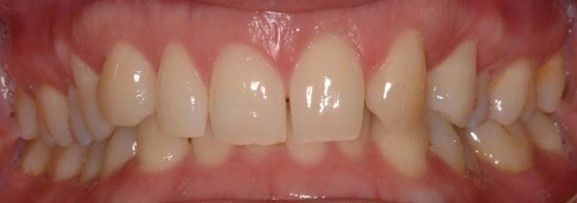

Debido a la agenesia congénita del incisivo lateral superior izquierdo, el paciente fue tratado 12 años atrás mediante ortodoncia convencional para cerrar el diastema (Figuras 1 y 2).

Tras el exhaustivo análisis clínico y radiográfico inicial, se le plantearon al paciente las diferentes alternativas terapéuticas (la reposición con una prótesis parcial removible, la realización de un puente tipo Maryland adhesivo, la confección de una prótesis parcial fija, o la colocación de un implante dental con su posterior restauración fija implantosoportada); todas ellas requerían del tratamiento previo multidisciplinar conjunto con un ortodoncista para la creación de un espacio mesial al canino. No se consideró pertinente abordar la situación clínica mediante restauraciones de composite y/o adhesivas, teniendo en cuenta la sobremordida de la paciente y considerando, por ello, la ortodoncia para mejorar la oclusión como la mejor opción.